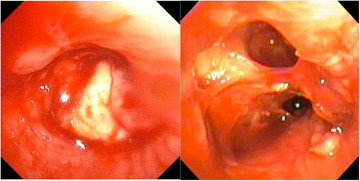

成人费城染色体阴性急性淋巴细胞白血病复发的发生率估计为40%-50%。异基因干细胞移植可提高复发性急性淋巴细胞白血病患者的生存率然而,肺功能受损对移植过程的存活是不利的。在此,我们报告一例成功的异基因移植治疗因血管浸润性肺毛霉菌病而完全切除左肺后复发的b急性淋巴细胞白血病。据我们所知,这是首例全肺切除术后同种异体移植成功的病例。该病例的具体考虑包括仔细的供体选择,明智地选择移植前调节方案,并利用新的免疫疗法确保移植前主要残留疾病阴性。我们希望这个病例能为临床医生提供额外的指导,帮助他们治疗恶性血液病患者,这些患者发展为侵袭性真菌感染,需要进行大的肺部手术。

The incidence of relapsed Philadelphia chromosome-negative acute lymphoblastic leukemia in adults is estimated to be 40%-50%. Allogeneic stem cell transplantation can improve survival in relapsed acute lymphoblastic leukemia; however, impaired pulmonary function is detrimental for surviving the transplantation process. Here, we present a successful case of allogeneic transplantation for relapsed B-acute lymphoblastic leukemia after total resection of the left lung due to angioinvasive pulmonary mucormycosis. To our knowledge, this is the first successful case of allogeneic transplantation after total pneumonectomy. Specific considerations in this case included careful donor selection, judicious choice of pre-transplantation conditioning regimen, and utilizing novel immunotherapies to ensure major residual disease negativity prior to transplant. It is our hope that this case provides additional guidance to clinicians caring for patients with hematologic malignancies who develop invasive fungal infections and require major lung surgeries.